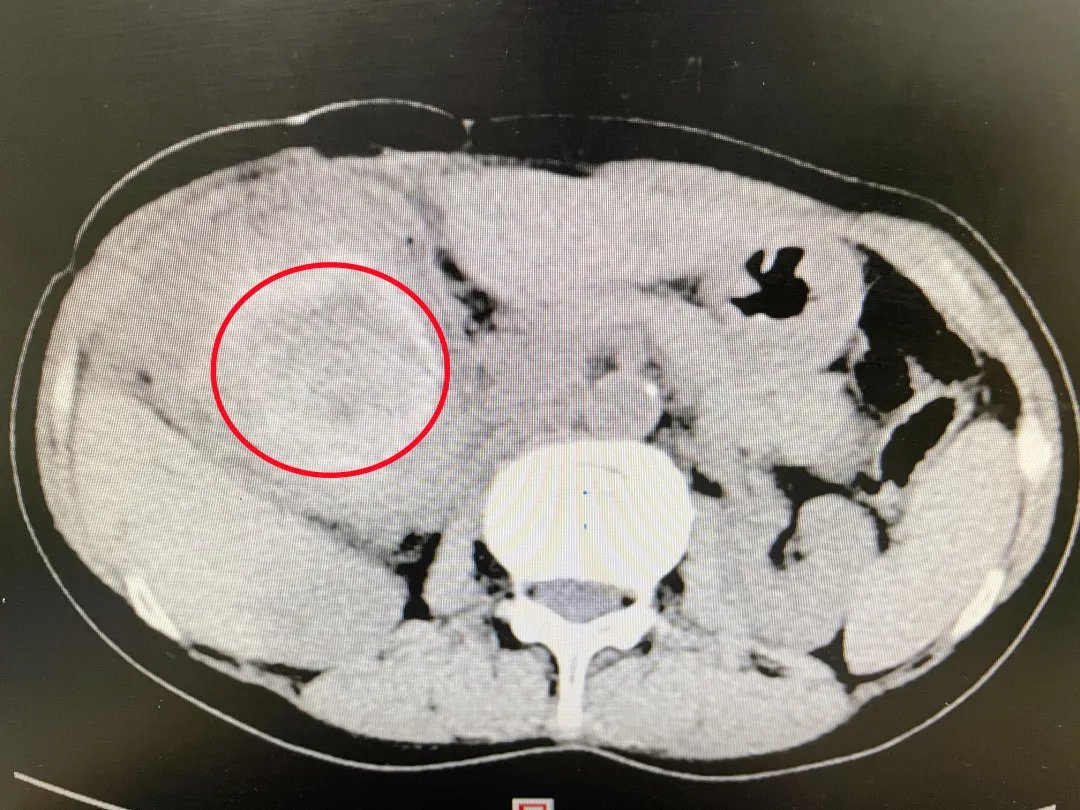

【 蛔虫|重234克直径12厘米!世界上最大的单颗胆总管结石成功摘除】术前CT显示,胆总管内有巨大结石(红圈所示)。